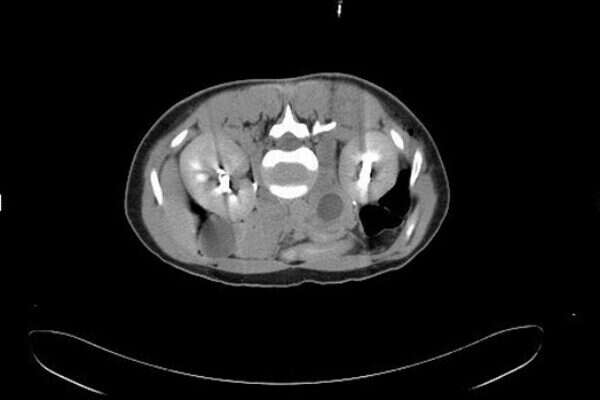

פעוטה שרק נולדה בהונג קונג אובחנה כמי שנמצאת בהריון עם תאומות. הפעוטה בת השלושה שבועות בלבד, שנולדה להורים מסין, נאלצה לעבור ניתוח וההערכה היא ששני העוברים היו כבר בני שמונה עד עשרה שבועות. בצילום אולטרסאונד הבחינו הרופאים ברגליים, ידיים, עמוד שדרה, צלעות ואפילו מעיים. השניים היו עטופים בעור, אחד מהם שקל 14.2 גרם ואילו השני שקל קצת פחות - 9.3 גרם. שניהם היו גם מחוברים בחבל הטבור.

הניתוח שעברה הפעוטה להסרת העוברים הוגדר כמוצלח והיא שוחררה מבית החולים שמונה ימים לאחר מכן. המקרה הנדיר והמדהים הזה התפרסם באופן מפורט בגיליון האחרון של המגזין הרפואי הונג קונג מדיקל ג'ורנל. התופעה, שנקראת בשפה המקצועית עובר עוברי מתרחש רק אחת לחצי מיליון לידות בעולם כולו. רק 200 מקרים כאלה דווחו בכלי התקשורת במהלך ההיסטוריה.

ד"ר יו קיי מאן, מומחה לילודה וגניקולוגיה טוען כי מדובר במקרה הראשון שתועד בעיר. "זה היה כמעט בלתי אפשרי לגלות את הדבר במהלך תהליך ההריון של הפעוטה, מכיוון שהעוברים בבטנה של הפעוטה (בזמן היותה עובר בעצמה), היו קטנים מידי", אמר יו לשעבר מרצה באוניברסיטת הונג קונג. "מכיוון שהפעוטה לא יכולה הייתה להיכנס להריון בעצמה, הזרע שקיבלה היא ככל הנראה מהוריה", מסביר ד"ר יו.